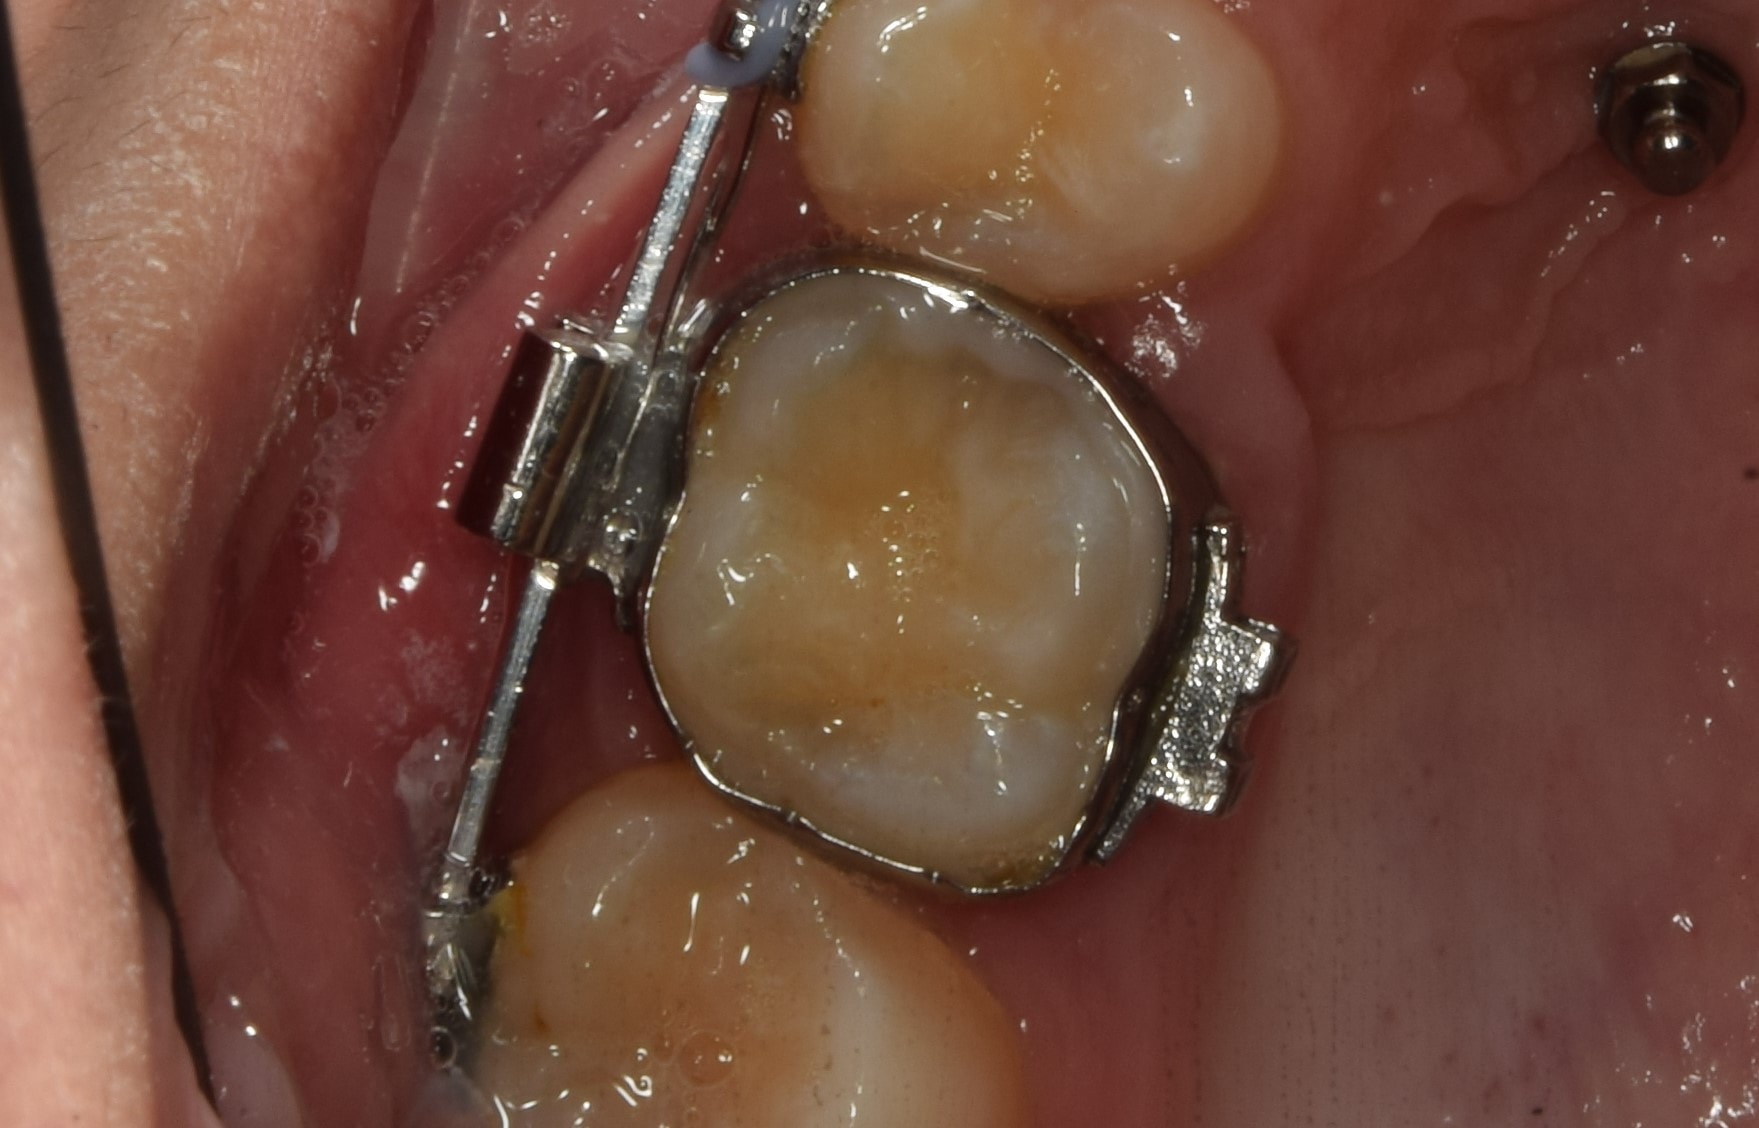

Gyűrű

Általában őrlőfogaknál használt, a teljes fogat körülölelő fém fogszabályzó alkotóelem, melyre tubus van hegesztve. Vannak olyan rögzített (EVA-platte) és kivehető (lip-bumper, Headgear) készülékek, amelyek használatához elengedhetetlen. A fogágyra igen negatív hatással van, ezért használatát minimálisra csökkentettem, de amikor szükséges, jó szolgálatot tesz.

Tubus

Tubusoknak nevezzük a nagyőrlőkre ragasztott rögzített fogszabályzó alkotóelemeket. Nevükben is benne van, hogy egy kis “alagutat” foglalnak magukba, ebbe lehet az íveket belecsúsztatni. A tubusokat általában nem lehet kinyitni, mint a bracketeket, néhány kivételtől eltekintve (önligírozó tubusok, konvertálható tubusok).